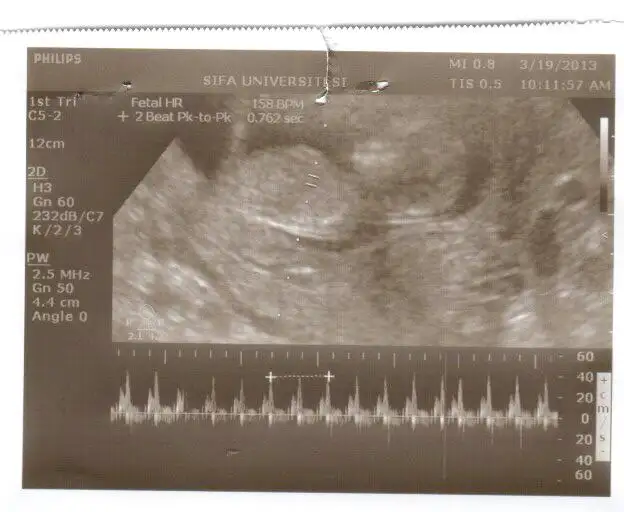

dr soylemeden siz gorun genital nub teorisi ( bebegin cinsiyeti)

KIZLAR BUDA BENİM BEBİŞİMİN 16+5 HAFTALIK SON RESMİ :nazar: